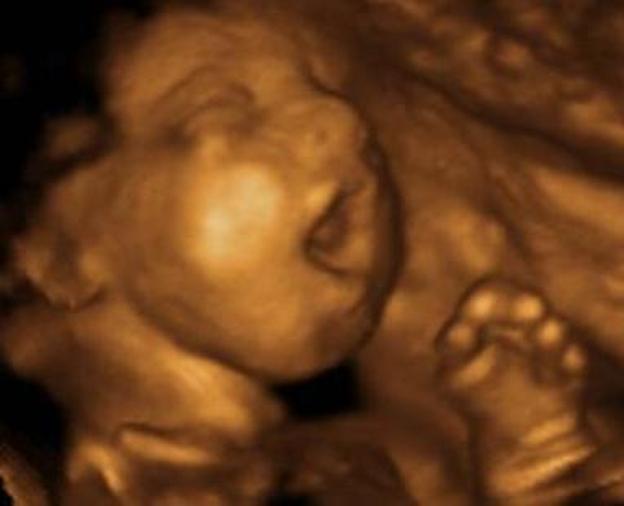

According to science, a fetus in the womb is capable of feeling pain once the heartbeat is detected. The most common forms of abortion in the United States are saline abortions, where the baby or fetus is burned out of the pregnant mother’s uterus.